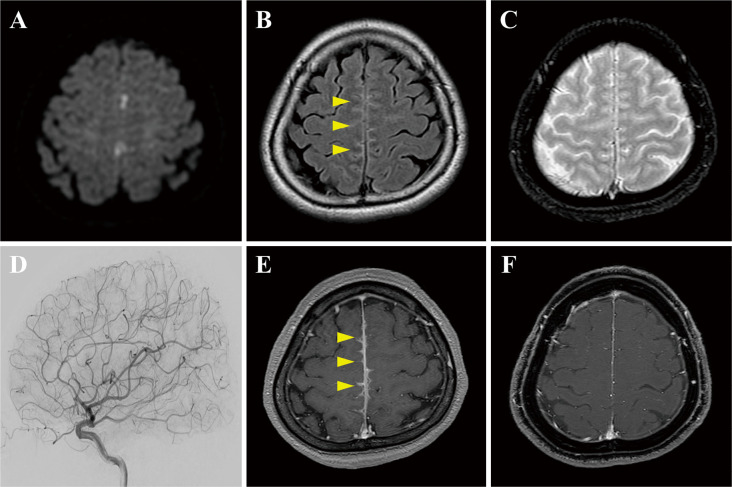

Presenting our MOG cohort from the Neuroimmunology UC team, highlighting real-world clinical data in MOGAD. #NeuroinmunoUC #MOGAD @TheMOGProject @SOCHEDEM1 @lactrims_org @EthelScl @adelcanto